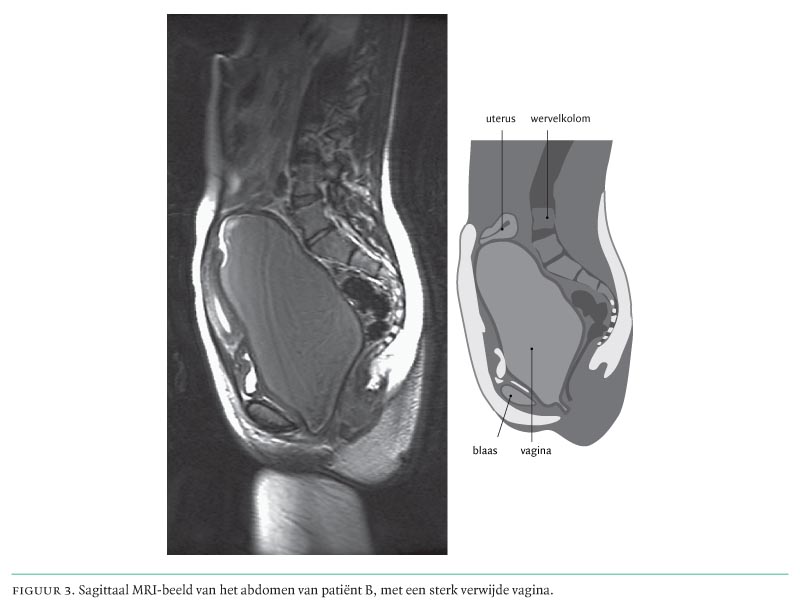

Een hymen imperforatus is een maagdenvlies dat de vagina volledig afsluit. Het is een ontwikkelingsstoornis die doorgaans geïsoleerd voorkomt. Onder normale omstandigheden heeft het hymen centraal een opening en kan vanaf de menarche het menstruatiebloed vanuit de uterus via de vagina naar buiten afvloeien. Wanneer de vagina naar distaal volledig is afgesloten, zal het bloed zich vanaf de eerste menstruatie in de vagina ophopen.